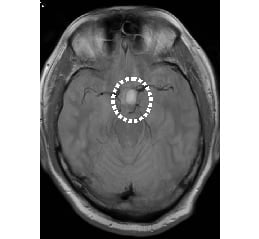

• MRI画像

脳腫瘍

脳梗塞